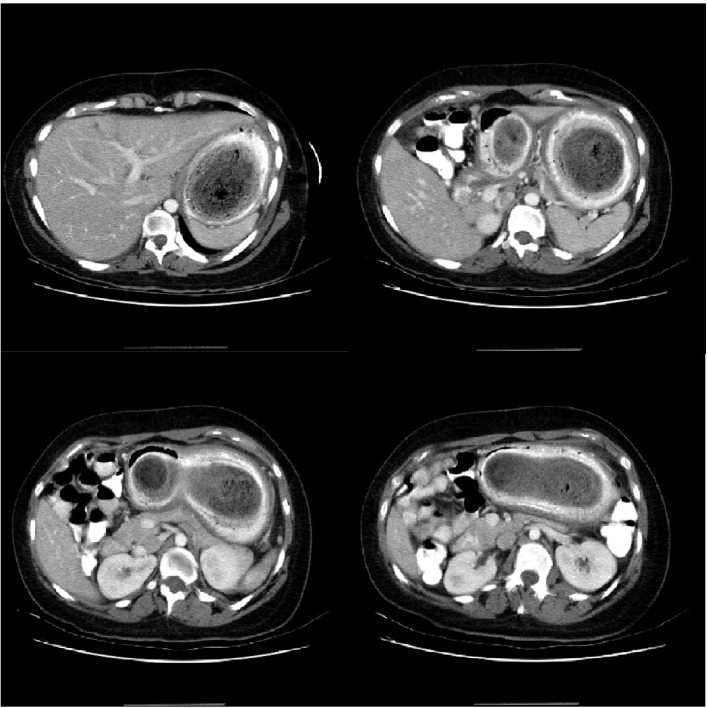

How Long Does a CT Scan of the Abdomen Take? Charlotte Radiology How Often Are Ct Scans Wrong But about a third of ct scans are not necessary and needlessly expose patients to radiation, according to health magazine, which recently took a closer look at the rewards and risks of medical. Some procedures require multiple scans over a region; You might have a very detailed scan of the bowel called a ct colonography (or virtual colonoscopy). Are certain. How Often Are Ct Scans Wrong.